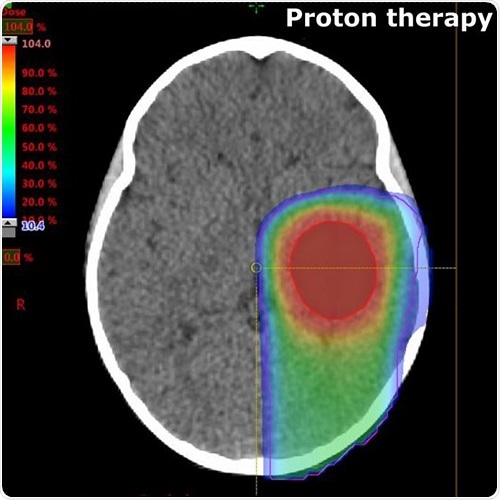

A typical radiation dose distribution for proton therapy

Compared to conventional x-ray (photon) therapy, proton beam therapy superiorly targets tumors and cancer cells, delivering optimal radiation doses to the tumor while limiting the effects on the surrounding healthy tissues.

Protons are designed to deposit radiation more conformally to the target volume, sparing both the healthy tissues before and beyond the target as well as critical structures surrounding the tumor.